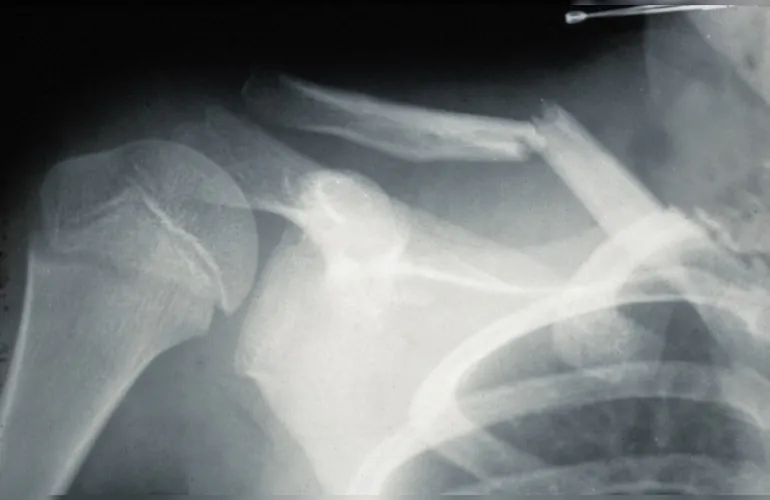

Perilunat çıkık, el bileğinde bulunan lunatum kemiğinin yerinde kalmasına rağmen, diğer el bileği kemiklerinin lunatum etrafında yer değiştirmesiyle oluşan bir çıkıktır.

Perilunat kırıklı çıkık, perilunat çıkığa ek olarak bir veya daha fazla el bileği kemiğinde kırık olması durumudur.

- Sıklıkla scaphoid, radius distal ucu, capitate gibi kemikler kırılır.